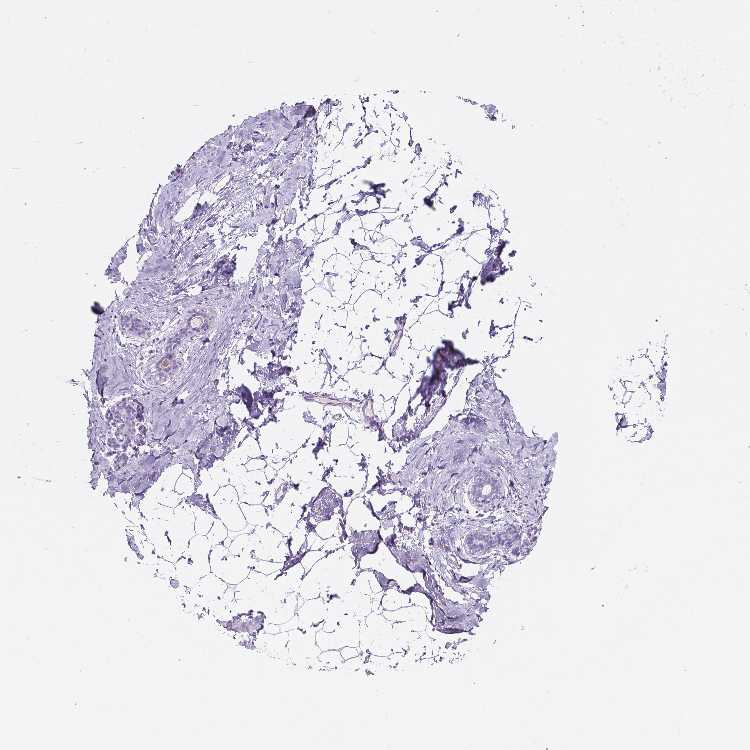

Female, age 52

Breast sample 373

nTPM: 1.6

Cell types%

Glandular cells:

15

Adipocytes:

5

Other cell types:

80

overview

Female, age 80

Breast sample 390

nTPM: 1.8

Female, age 47

Breast sample 405

nTPM: 2.1

90

Female, age 38

Breast sample 410

nTPM: 3.3

40

55